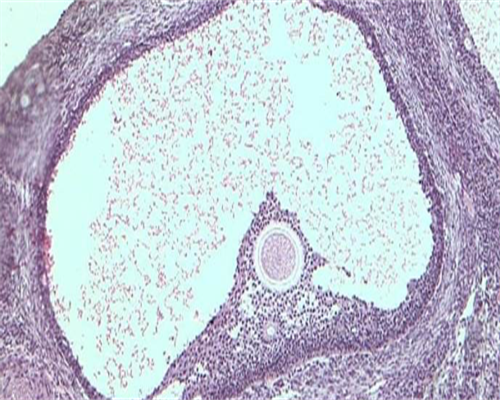

使用促排卵药物,促使卵泡长大并成熟,从而将女方卵巢里的药物促排起来较多的卵子取出,这些药物科学使用不会对女性造成不良影响,取卵后也不会造成女性卵巢功能的减退,所以试管婴儿不会导致提前衰老,提前衰老主要是因为身体内的雌激素变少引起的,经常熬夜,生活不规律,导致内分泌紊乱,也可以导致提前衰老。